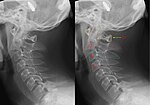

Hangman's fracture Hangman fracture of both pedicles of C2 distraction and extension of neck Hangman's fracture Archived 2020-09-18 at the Wayback Machine at Wheeless' Textbook of Orthopaedics online Hangman's fracture.JPG